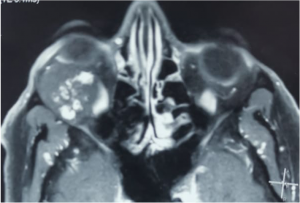

| Carotid-Cavernous Fistula[25] | No age/ gender predilection | Direct – sudden pulsatile exophthalmos, conjunctival chemosis, with dilated episcleral vessels and bruit.

|

USG Doppler – shows increased velocity with reversal of blood flow direction, dilated Superior Ophthalmic Vein (SOV) and arterial pulsations.

CT/MRI - proptosis, EOM enlargement, dilated and tortuous SOV, with engorgement and early enhancement of the ipsilateral cavernous sinus. CT Angiography- differentiate direct and indirect CCF but cerebral angiography is used for accurate diagnosis and intervention. |

Traumatic carotid-cavernous fistula) Axial T2WI MRI of right orbit showing dilated superior ophthalmic vein along its whole course (orange arrow) b) Coronal T2WI MRI showing dilated superior ophthalmic vein (white dotted arrow) with engorgement of the extra ocular muscles compared to the contralateral normal side (orange arrows) |